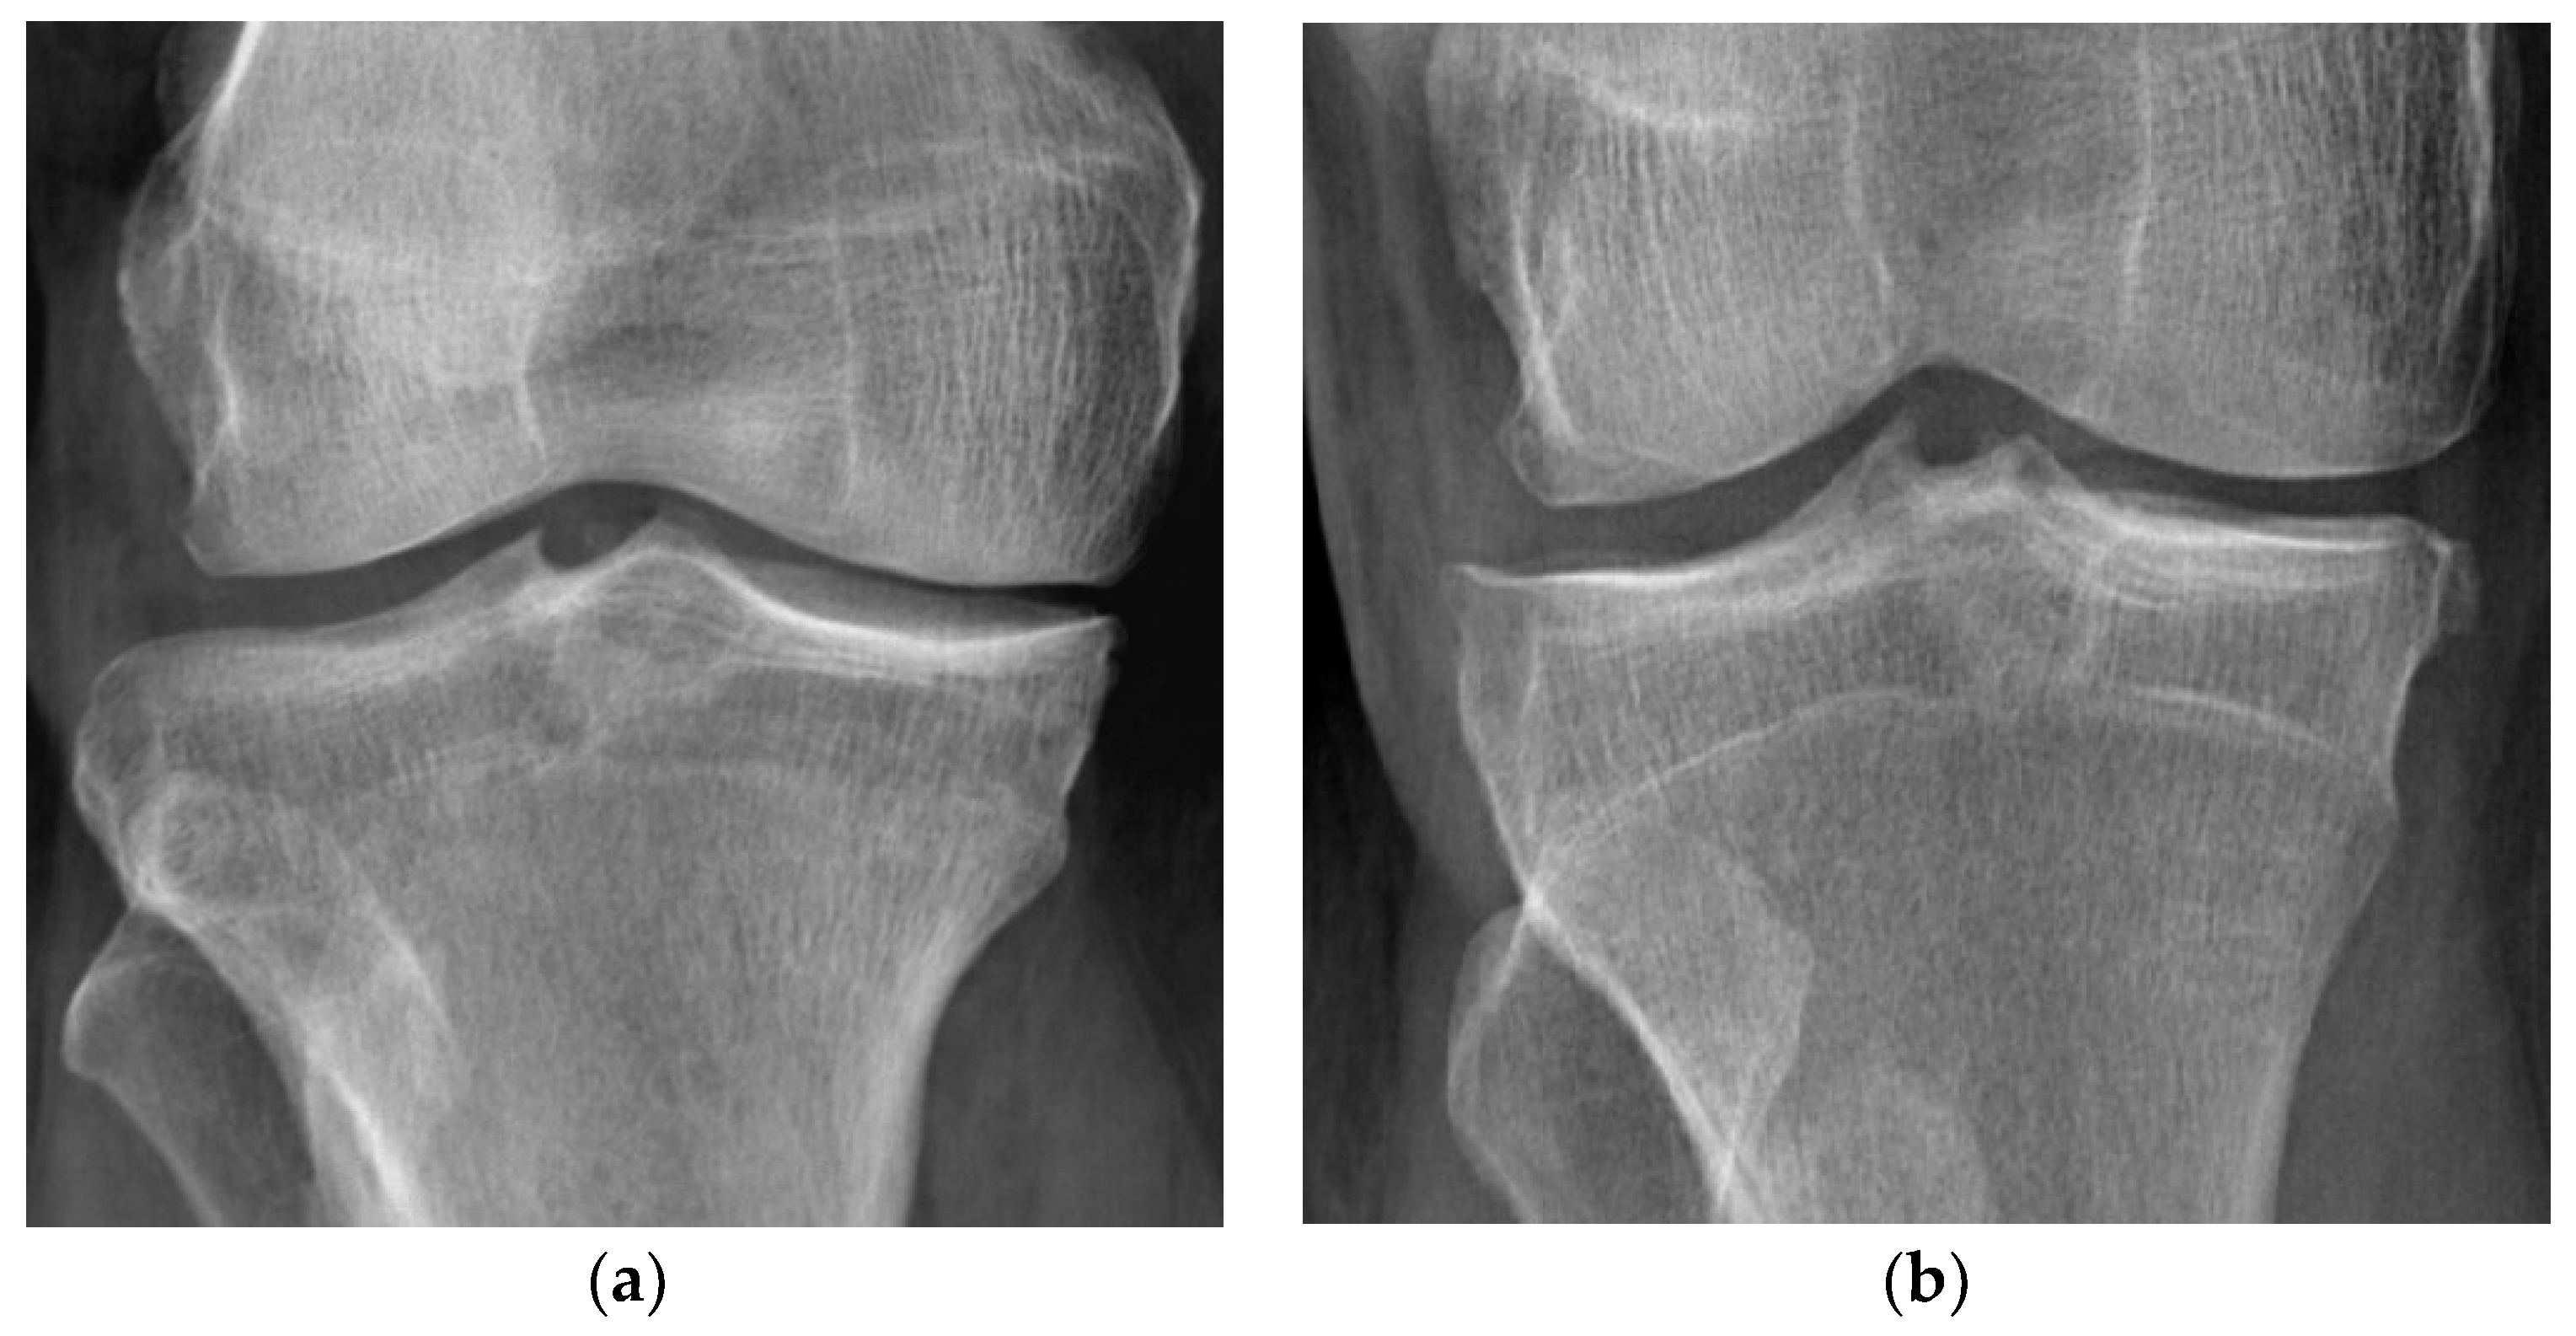

| KL | Kellgren–Lawrence classification |

- Kohn, M.D.; Sassoon, A.A.; Fernando, N.D. Classifications in Brief: Kellgren-Lawrence Classification of Osteoarthritis. Clin. Orthop. Relat. Res. 2016, 474, 1886–1893. [Google Scholar] [CrossRef]